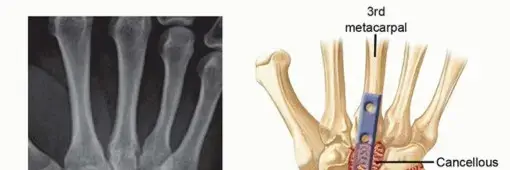

كما ذكرنا سابقًا، هو إجراء جراحي يهدف إلى دمج عظام الرسغ معًا لتشكيل عظم واحد صلب ومستقر. يتم ذلك عن طريق إزالة الغضاريف التالفة من نهايات العظام، ثم تثبيت العظام في وضع وظيفي باستخدام ألواح ومسامير معدنية. بمرور الوقت، تلتئم العظام وتلتحم معًا، مما يُنهي مصدر الألم.

5. التثبيت: تُستخدم لوحة معدنية ومسامير لتثبيت العظام معًا بشكل آمن. تُصمم هذه الألواح خصيصًا لتوفير أقصى قدر من الاستقرار حتى تلتئم العظام.

6. الطعم العظمي (إذا لزم الأمر): في بعض الحالات، قد يستخدم الجراح طعمًا عظميًا (سواء من جسم المريض نفسه أو من بنك العظام) للمساعدة في تسريع عملية الالتئام والدمج بين العظام.